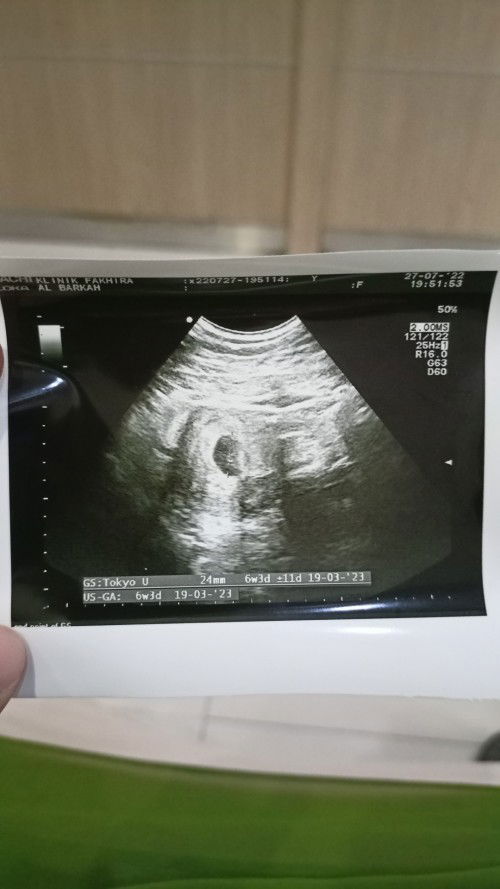

Hasil USG 6 Minggu

Yg hamil 6w itu klo usg keliatan apa aja sih? Apa udh keliatan calon bayinya atau masih kantung kehamilan aja